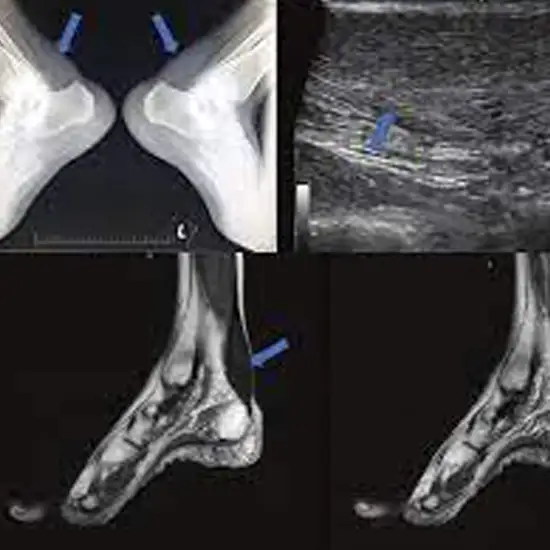

NCCT Right Ankle Joint is a non-contrast CT scan of the right ankle Joint. This non-invasive examination is used for the evaluation of bony and soft tissue abnormalities in the right ankle. It is considered an effective diagnostic methodology to diagnose Ankle Joint injury to the tendon, fracture to the bone, and infections of the right ankle. Because other testing techniques such as X-ray don’t give clarity about soft tissue problems.

It is also used as a quick examination tool to identify traumatic injuries to the right ankle after an accident.